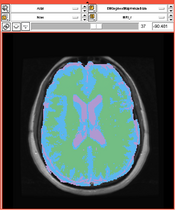

Brain Atrophy in Aging Patients

- Collaborator: David Tate, PI (Brigham and Women's Hospital), Daniel McCaffrey (Brigham and Women's Hospital), Alex Zaitsev (Brigham and Women's Hospital/Surgical Planning Laboratory) and Jewish Hospital

- Short description: Evaluate Brain Atrophy in aging subjects (NOTE: the segmentation was done for old scans from 90s. No other tools could segment CSF.)

- Image specification: NA Tesla, Scanner: NA, Psuedo T1, Axial Scans, TR/TI/TE=NA, pixel_xsize = 0.937500, pixel_ysize = 0.937500, fov = 240.000000, aspect = 0.000000, thick = 5.000000

- Used Task: MRI Human Brain